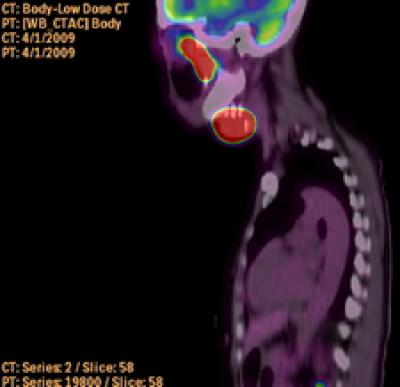

April 28, 2009 – (BRONX, NY) – A laboratory study by researchers at Albert Einstein College of Medicine of Yeshiva University suggests that an anti-cancer compound studied for treating blood cancers may also help in treating cancers of the head and neck. The work is reported in the April 28th online edition of the Journal of Pathology .

Head and neck cancer refers to tumors in the mouth, throat, or larynx (voice box). Each year about 40,000 men and women develop head and neck cancer in the U.S., making it the country's sixth-most common type. Surgery, chemotherapy and/or radiation are the main treatment options but can cause serious side effects. Better treatments are needed, since only about half of patients with head and neck cancer survive for five or more years after diagnosis.

The Einstein study involved a new class of chemotherapy agents known as histone deacetylase (HDAC) inhibitors, which affect the availability of genes that are transcribed and translated into proteins. In many types of cancer, out-of-control cell growth results from certain genes that are either too active or not active enough in producing proteins. HDAC inhibitors appear to combat cancer by restoring the normal expression of key regulatory genes that control cell growth and survival.

The Einstein researchers focused on a particular HDAC inhibitor known as LBH589 that has already shown some success in clinical trials involving people with cancers of the blood. The researchers found that LBH589 succeeded in killing tumor cells that had been removed from head and neck cancer patients and grown in the laboratory.